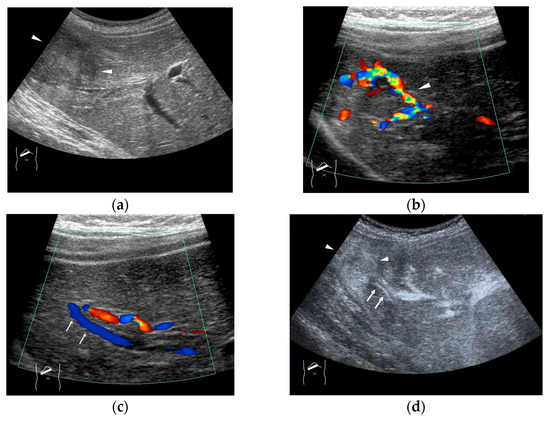

4. HV Hemodynamic Changes (Vascular Shunts) in Non-Tumor-Related Livers

4.1. HHT-Related HV Abnormalities

4.2. Congenital P-V Shunts

4.3. Budd–Chiari Syndrome